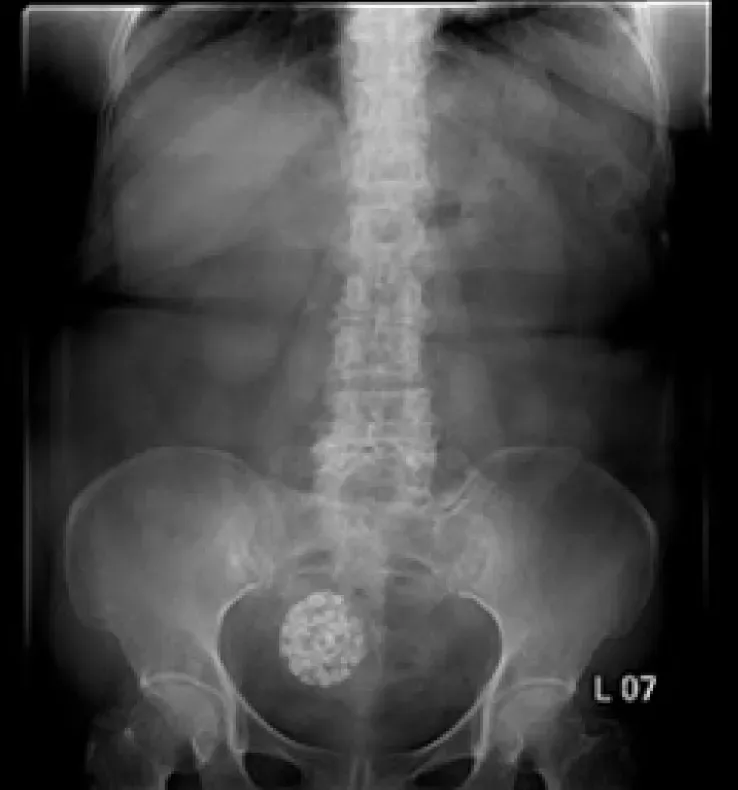

【115-1 醫學(六) 第74題】65 歲女性病人因腹痛接受腹部X光檢查如附圖。最可能之診斷為何?